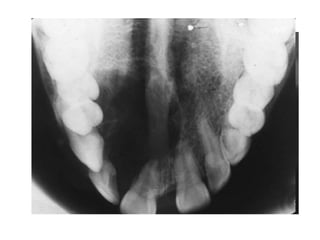

Radiología.

• Lesión uni o

multilocular

radiolúcida.

• De bordes o límites

netos o difusos

(dependiendo de su

clasificación)

• Tamaño 5mm a 10 cm